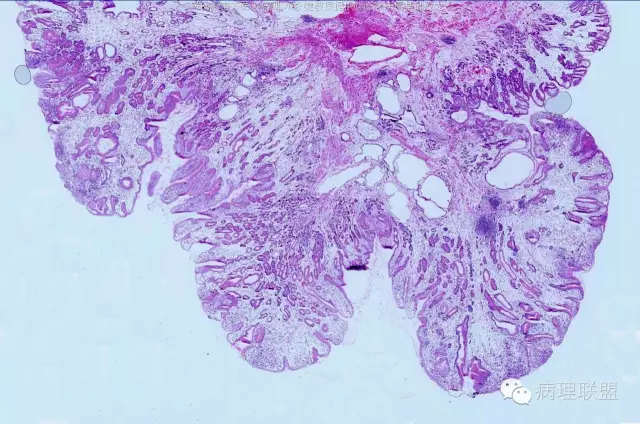

男,58岁,胃窦2.5×2.1×1.5cm大小肿物。冰冻切片。(病例由南方医科大学 邓永键教授提供,致谢!)

平滑肌束进入病变中,重点是表面腺体与正常腺体类似。

错构瘤性息肉/Peutz-Jephers息肉,在胃体,表面腺体是胃体腺,胃窦部是粘液腺;在小肠、大肠,表面腺腺体是小肠腺、大肠腺。该病变可以从食管至肛门都可发生。如果不出现出血、溃疡、梗阻症状,不体检,病人不会出现症状,不易被发现。小肠发生,易致肠梗阻、肠扭转。肛门发生,可脱出似内痔。